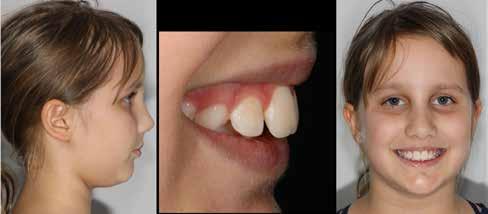

Lány páciensem I. fázisú kezelését 10 évesen kezdtük el bimaxilláris funkciós, kivehető készülékkel. Megfigyelhetőek a class 2-es eltérésnél tipikusan jellemző szűk felső és alsó fo-

gívek, valamint a nagy overjet, a mandibula disztál helyzete, továbbá a felső metszőfogak protrúziója, amelynek kialakulásához sokszor hozzájárul az ujjszopás is (1-3. képek)

A második fázisú kezelés Pitts-21-es fix fogszabályozó készülék alkalmazásával történt meg. A Pitts elveknek megfelelően a kezelési célok a felső középső metszőfogak megfelelő pozicionálása, a 12 fogas (6-ostól – 6-osig) mosoly, az ideális íves lefutású mosolyvonal kialakítása, továbbá az okklúzió finomítása voltak. Mint mindig, a felső fogíven mosolyvonal beállító esztétikai pozicionálást (Smile Arc Protection - SAP) alkalmaztunk, a mes-

terséges harapásemelés pedig az alsó hatosokra, majd később a felső négyesekre került (8. kép). Az intermaxilláris elasztikus gumihúzás class-2-ess vektorú volt annak érdekében, hogy a disztálharapás korrekciója tökéletes legyen (9. kép). A harapást beállító elasztikus gumihúzásokat – mint minden kezelésnél –, ebben az esetben is folyamatosan, az egész kezelés alatt 24 órában (étkezések kivételével) viselte páciensünk.

A második Pitts-21 fix készülékes fázis ideje 16 hónap volt (10-12. képek)